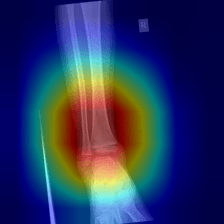

Sample: Oblique Displaced Fracture

Figure 3. Left: Raw X-ray of an Oblique Displaced fracture. Right: HyperColumn-CBAM DenseNet-169 Grad-CAM activation map highlighting the fracture region and surrounding cortical context.